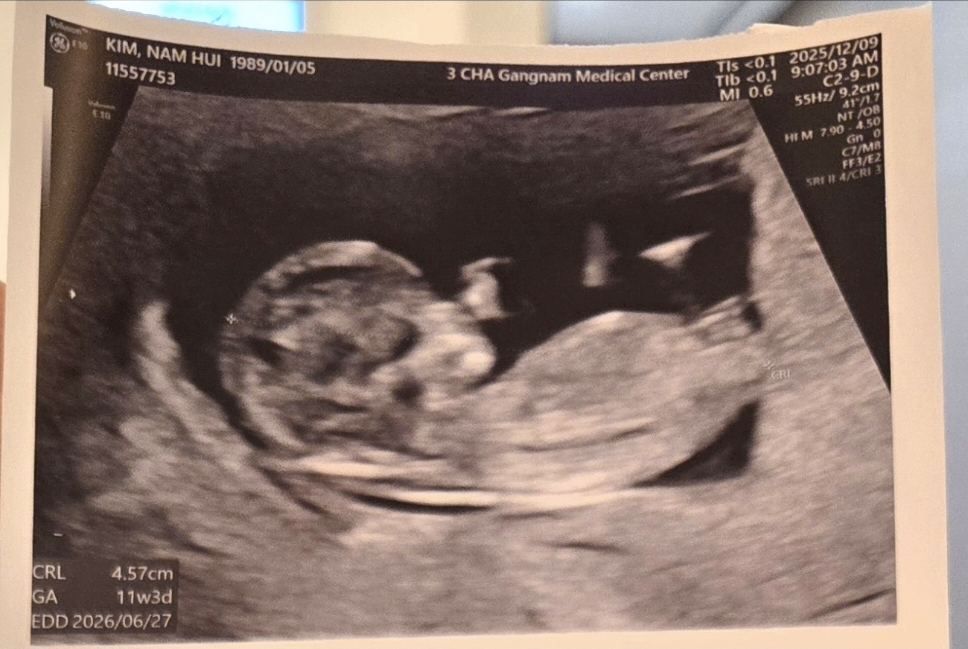

11주인데요

아들일까요 딸일까요?